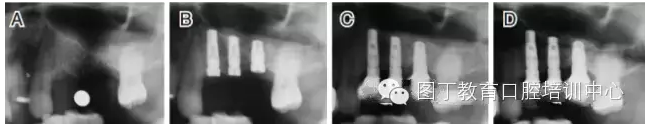

病例4 植入骨替代材料(圖6)

圖6